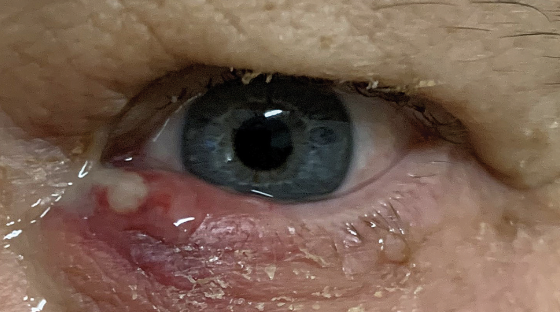

Chalazion

Abnormalities of the External Eye

Infected meibomian gland

Hordeolum

Abnormalities of the External Eye

Stye

Seborrhea or Blepharitis

Hordeolum (Stye)

Chalazion

Abnormal Findings for 5. Redness, swelling, discharge, or lesions

Hordeolum (Stye)

Abnormal Findings for 5. Redness, swelling, discharge, or lesions

Hair follicle infection, causes local redness, swelling, and pain

Chalazion

Abnormal Findings for 5. Redness, swelling, discharge, or lesions

Infection of the meibomian gland (located in the eyelid)

May produce extreme swelling of the lid, moderate redness, but minimal pain